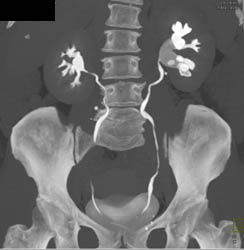

Acute Pyelonephritis Right Kidney